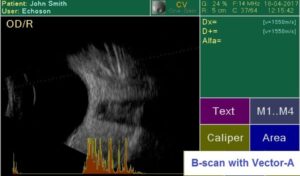

Современный ультразвуковой офтальмологический сканер для визуализации, биометрии и пахиметрии глаза.

Визуализация структуры глаза.

Сенсорный экран (легкое использование благодаря понятному меню, виртуальная клавиатура для ввода данных пациента); внешняя USB клавиатура (опция), цветной 7″ LCD экран, 800×480 пикселей; десять (10) профилей пользователя; запись изображений на внешний USB накопитель; встроенный термопринтер; легкое обновление программного обеспечения через USB порт; USB порт для внешнего лазерного принтера; 6 типов отчета.